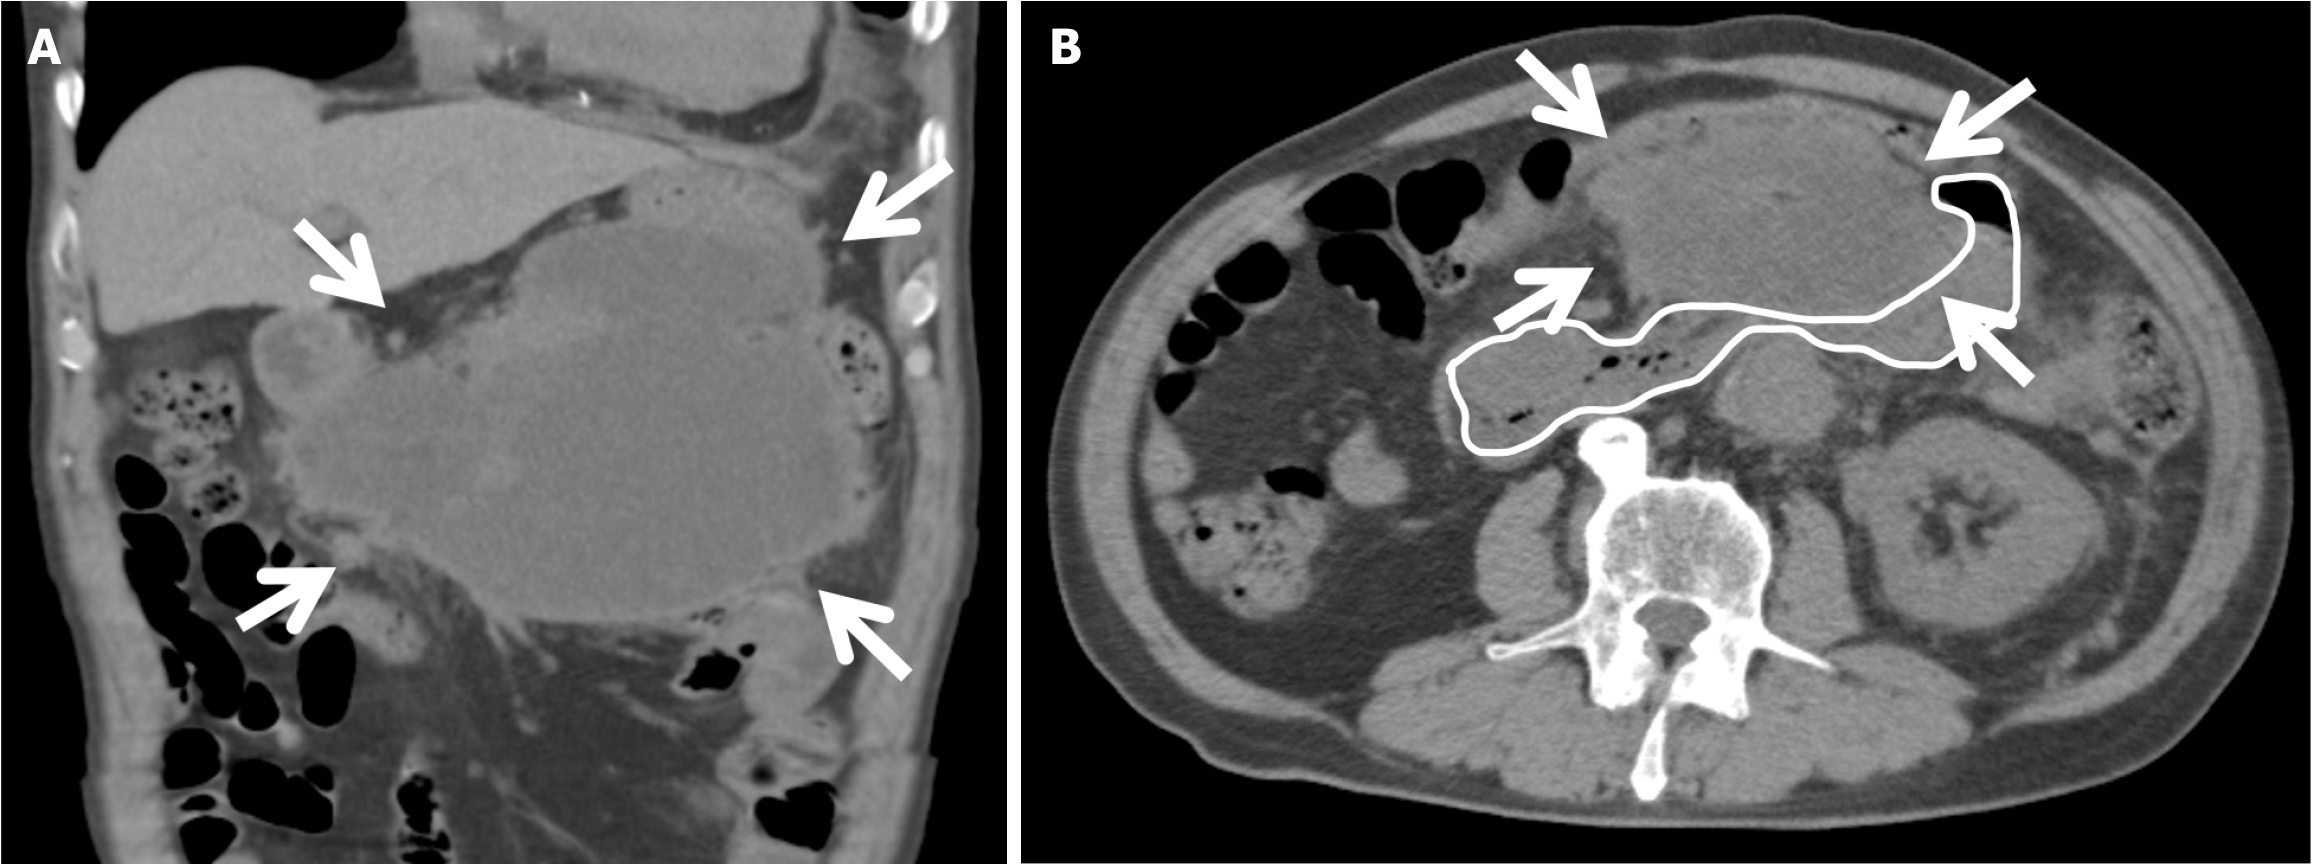

Figure 2 Computed tomography on postoperative day 42.

These computed tomography showed that the walled-off necrosis (arrows) was compressing the horizontal part of the duodenum (outlined in the white line). A: Coronal; B: Axial.